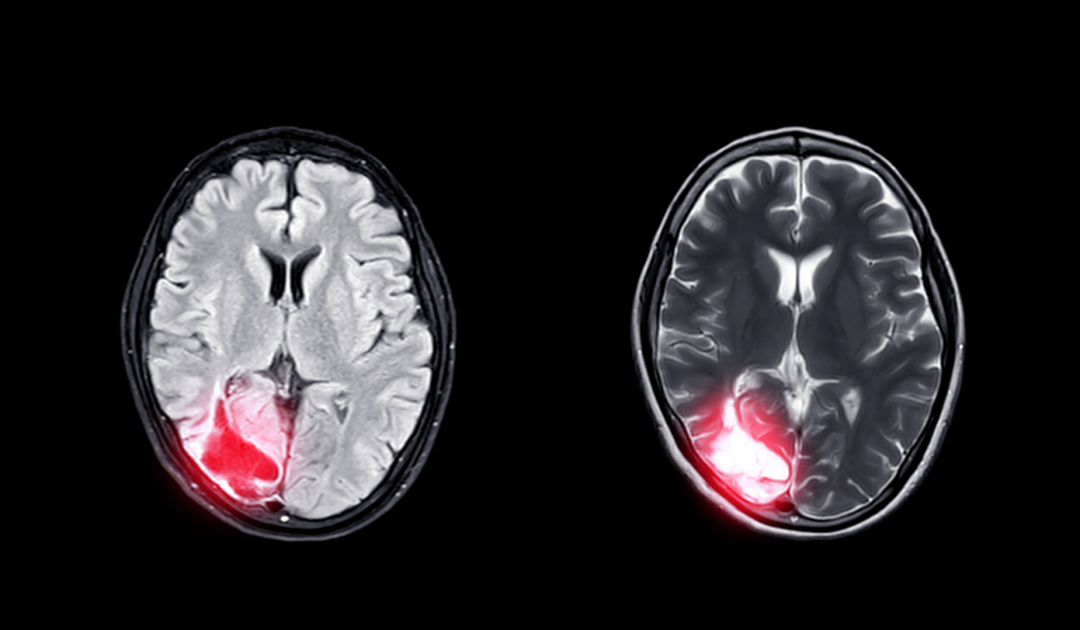

大脑作为人体的「司令官」,必须保证充足的血液供应才能够完成一系列生命活动,供血不足若不及时治疗,很可能引起痴呆、突然晕厥,甚至猝死、脑梗死等现象,必须给予足够的重视。

如果出现头晕头痛、失眠多梦、耳鸣、记忆力明显减退、肢体麻木等症状,且持续 2 个月以上,应及时就医进行脑电图、脑 CT 血管造影、核磁共振血管造影、经颅多普勒超声等相关检查,以便确诊。